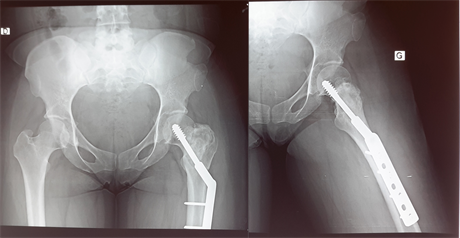

Figure 3. X-ray after curettage, filling by a graft of the iliac crest and stabilization by DHS.

A biopsy was performed and the diagnosis of GCT was made and classified as stage II of Enneking. We proceeded, by a Watson-Jones approch, to a careful curettage with cauterization of the bone walls with the electric scalpel. The residual cavity was filled by a tri cortical graft of the iliac crest and a stabilization by dynamic hip screw was made (Figure 3).

At six months postoperative, the patient was asymptomatic. A good fusion of the bone graft was noted (Figure 4).

At two years of age, the patient was still asymptomatic and the radiographs showed no recurrence (Figure 5).